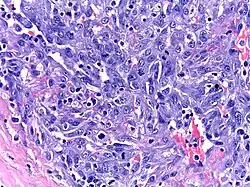

Patients with HHV-8-associated MCD are often found to have Kaposi sarcoma,[1] a cancer caused by the HHV-8 virus and most commonly seen in patients with HIV. Patients with HHV-8-associated MCD have been observed to be at greater risk of developing lymphoma.[3]

Micrograph of a Kaposi sarcoma in a lymph node biopsy of a patient with HHV8-associated MCD.